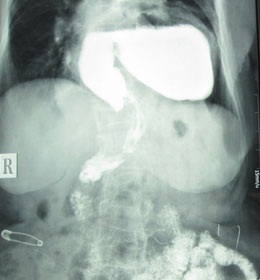

Hình ảnh siêu âm lồng ngực của bệnh nhân, do Bệnh viện Nhân Dân Gia Định cung cấp

Qua xét nghiệm, chẩn đoán hình ảnh bác sĩ phát hiện bà Y. bị thoát vị khe hoành thực quản khổng lồ khiến toàn bộ dạ dày và một phần ruột già nằm trên lồng ngực bệnh nhân.